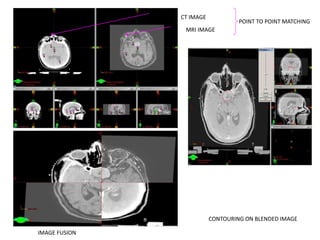

Image registration

• The term image registration -- a process of

correlating different image data sets to identify

corresponding structures or regions.

• Allows full voxel to voxel intensity match

• Image Fusion automatically correlates thousands

of points from two image sets, providing true

volumetric fusion of anatomical data sets.

• For example--, mapping of structures seen in MRI onto

the CT images.

• Various registration techniques include

– Point-to-point fitting,

– Line or curve matching

– Surface or topography matching

– Volume matching

MRI IMAGE

CT IMAGE

CONTOURING ON BLENDED IMAGE

POINT TO POINT MATCHING

IMAGE FUSION